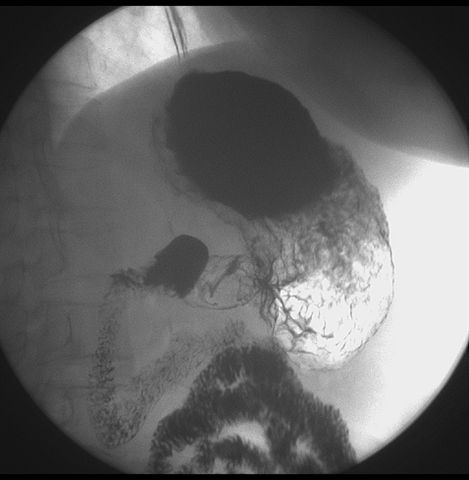

标题: X6872:F,69y,胃部不适。

胃窦至幽门段胃壁僵硬,扩张受限,局部纠集粘破坏,呈杵状。提示溃疡癌变可能性大。

胃窦癌可能性大,建议胃镜活检。钡剂太稀,吃的有点多。

支持考虑胃窦癌可能,胃内滞留液太多,胃窦部僵硬。

胃窦部见钡池影,局部粘膜紊乱,纠集呈杵状改变,胃壁扩张受限,胃窦癌可能性大,建议胃镜检查.

胃窦部管腔扩张度较差,形态略有改变,胃窦粘膜显示欠佳,胃窦部占位可能性大,结合胃镜活检。

胃窦部狭窄、稍僵硬,考虑胃窦癌?建议胃镜检查。

北京肿瘤医院胃镜诊断皮革胃。